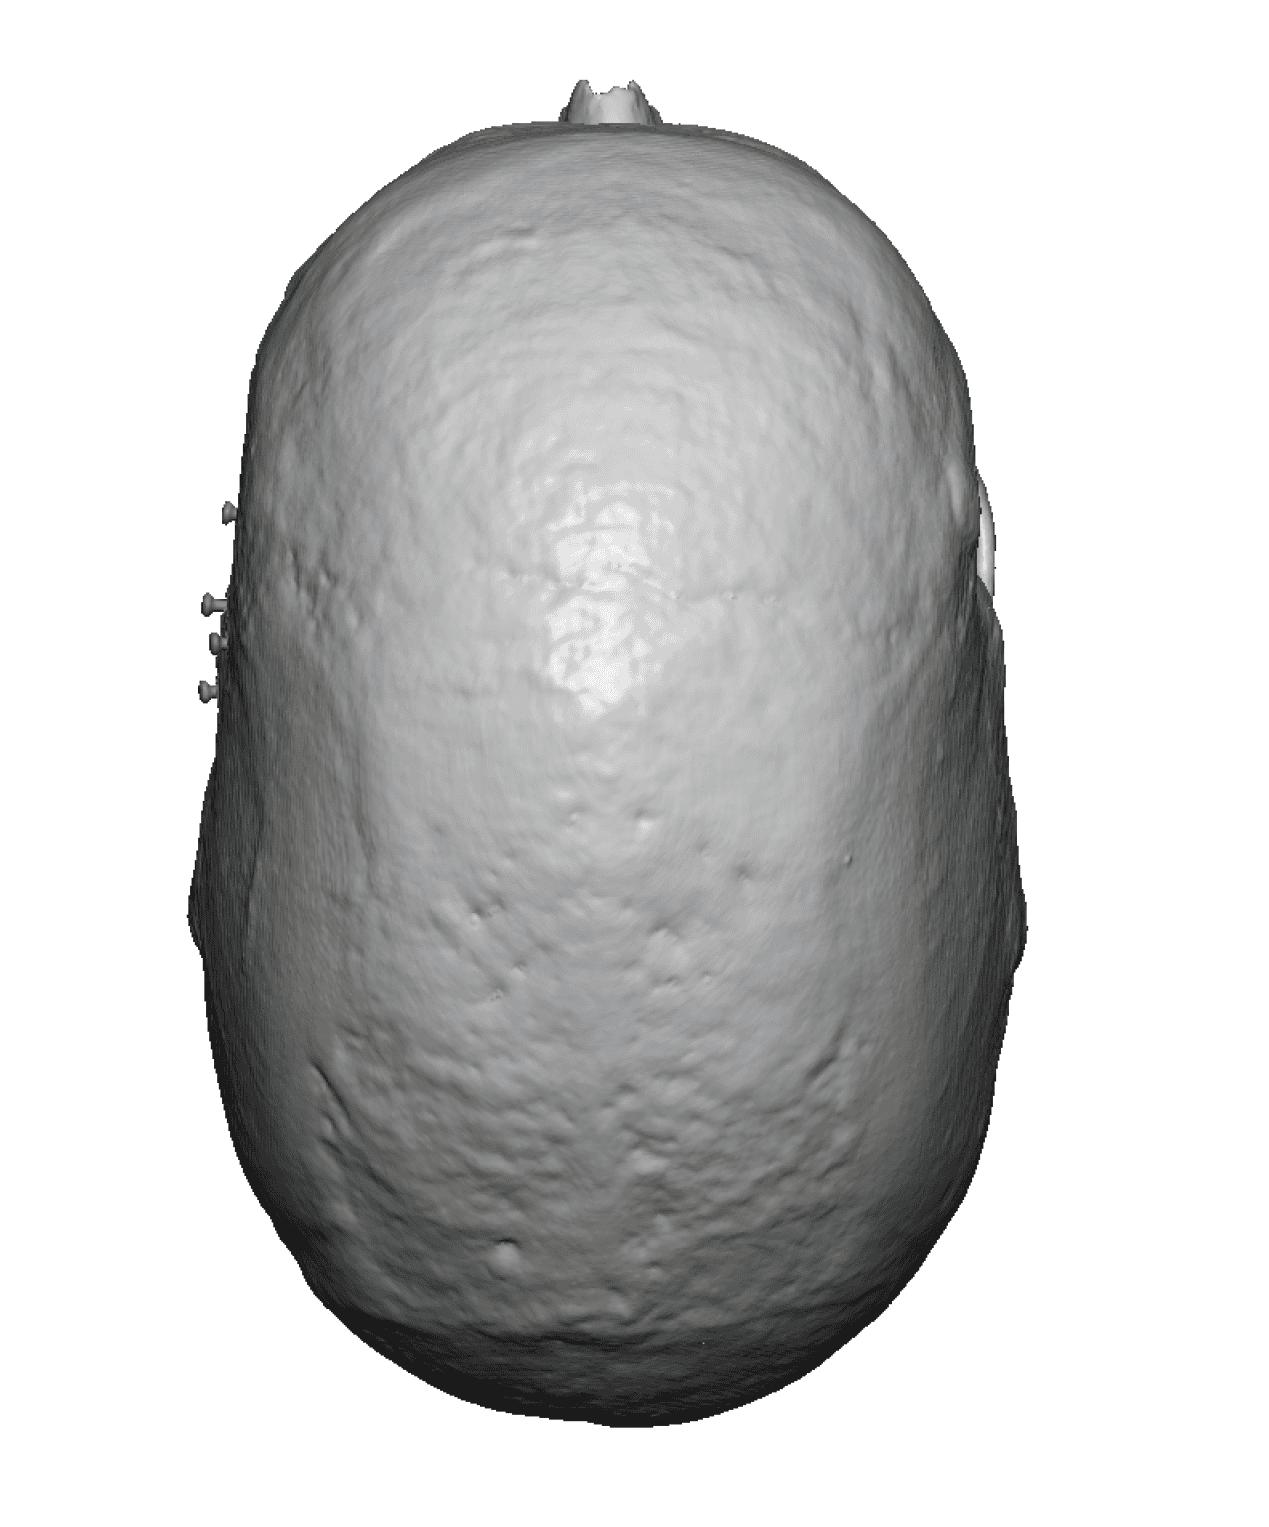

Severe narrowing skull deformity from prior sagittal craniosynostosis repair as an adult.

Complete replacement of entire skull by a custom implant with temporal fat injections.

Severe narrowing skull deformity from prior sagittal craniosynostosis repair as an adult.

Complete replacement of entire skull by a custom implant with temporal fat injections.